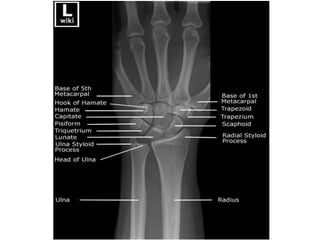

Wrist & Hand

Hand and Wrist

Appearance(Years)

• 1st – lower end radius, capitate,

hamate

• 2nd – Head of 2,3,4,5th

metacarpal, bases of proximal

phalanges

• 3rd – Triquetral, base of first

metacarpal, middle and

terminal phalanges

• 4th – lunate

• 5th – trapezium,trapezoid,

scaphoid

• 6th – lower end of ulna

• 12th- Pisiform

Hand and Wrist Appearance(Years) •1st – lower end radius, capitate, hamate • 2nd – Head of 2,3,4,5th metacarpal, bases of proximal phalanges • 3rd – Triquetral, base of first metacarpal, middle and terminal phalanges • 4th – lunate • 5th – trapezium,trapezoid, scaphoid • 6th – lower end of ulna • 12th- Pisiform Fusion(Years) • 17th – base of first metacarpal • 18th – epiphysis of metacarpals, phalanges and lower end of ulna • 19th – lower end of radius